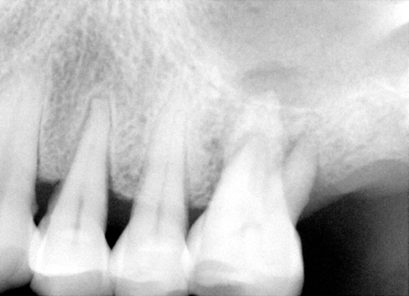

| 图一 术前根尖片左上6号牙根尖阴影阳性 | 图二 术前根尖片左上6号牙根尖阴影阳性 |

检查:面部对称,没有肿胀,没有牙关紧闭,口腔卫生尚可,多个修复物(补牙),左上7号牙缺失,左上6号没有蛀牙,牙龈退缩,4毫米牙周袋,轻度扣痛,没有窭道。根尖片(图一,图二)显示:左上6号牙骨质吸收,根尖有阴影。